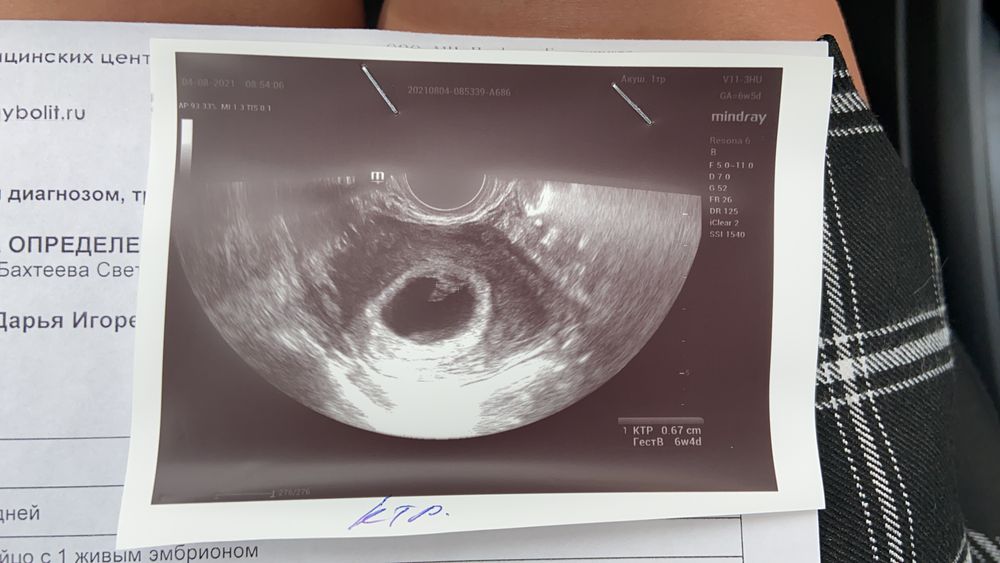

наконец-то я дождалась наше первое узи!🥰 с креветочкой все хорошо, всё соответствует сроку, маленькое сердечко бьется!🤍 ПДР по первому УЗИ поставили на 25-26.03.2022, жду малень